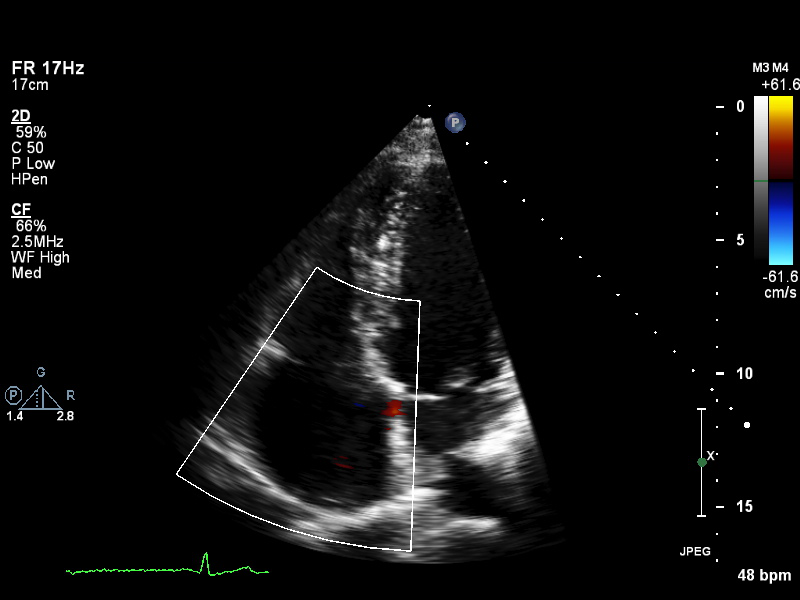

Doppler (8 views)

ImageView NameDescription

doppler-ao doppler-ao Spectral Doppler of the descending aorta

doppler-av doppler-av Spectral Doppler of the aortic valve

doppler-mv doppler-mv Spectral Doppler of the mitral valve

doppler-pv doppler-pv Spectral Doppler of the pulmonary valve

doppler-tissue-lateral doppler-tissue-lateral Tissue Doppler of the LV lateral wall

doppler-tissue-rv doppler-tissue-rv Tissue Doppler of the RV free wall

doppler-tissue-septal doppler-tissue-septal Tissue Doppler of the LV septal wall

doppler-tv doppler-tv Spectral Doppler of the tricuspid valve